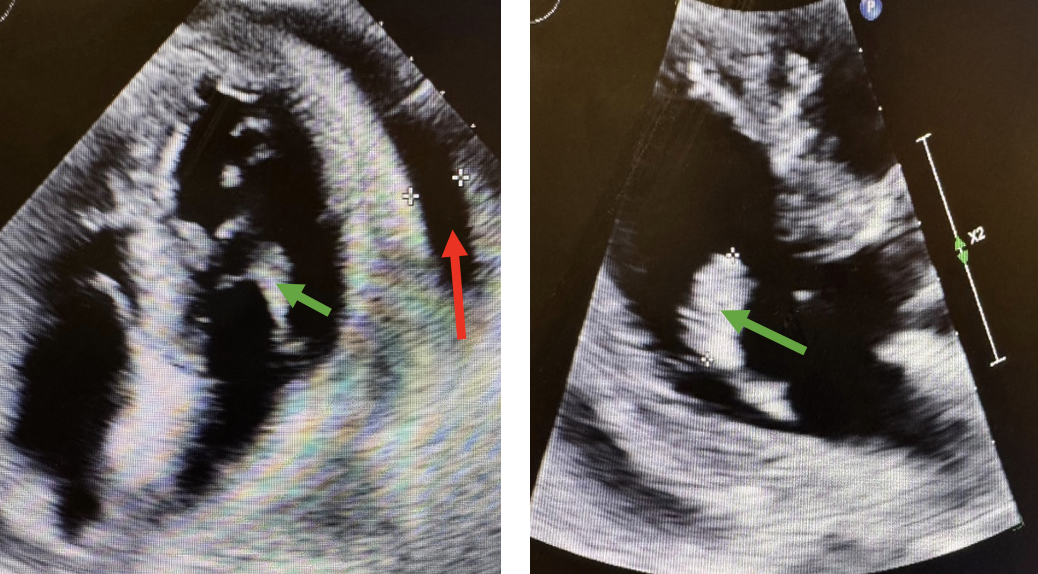

Case: A 65-year-old woman with end-stage renal disease status post renal transplant and on chronic immunosuppression presented with two days of worsening dyspnea. She was hypotensive and tachycardic but afebrile and without leukocytosis. TTE showed a moderate pericardial effusion with early tamponade physiology and a partially mobile 1.8 × 1.0 cm mass attached to the posteromedial papillary muscle, interpreted as tumor or thrombus (Figure 1). Cardiac MRI was recommended but deferred due to instability. CT chest with contrast revealed several pulmonary nodules, two masses in the right breast, and an enlarged mediastinal lymph node—findings suggestive of widespread malignancy (Figure 2). The patient then exhibited altered mental status, prompting a CT scan of the head, which identified ring-enhancing lesions in the brain (Figure 3). Subsequently, samples of blood and pericardial fluid revealed the presence of disseminated Aspergillus fumigatus.